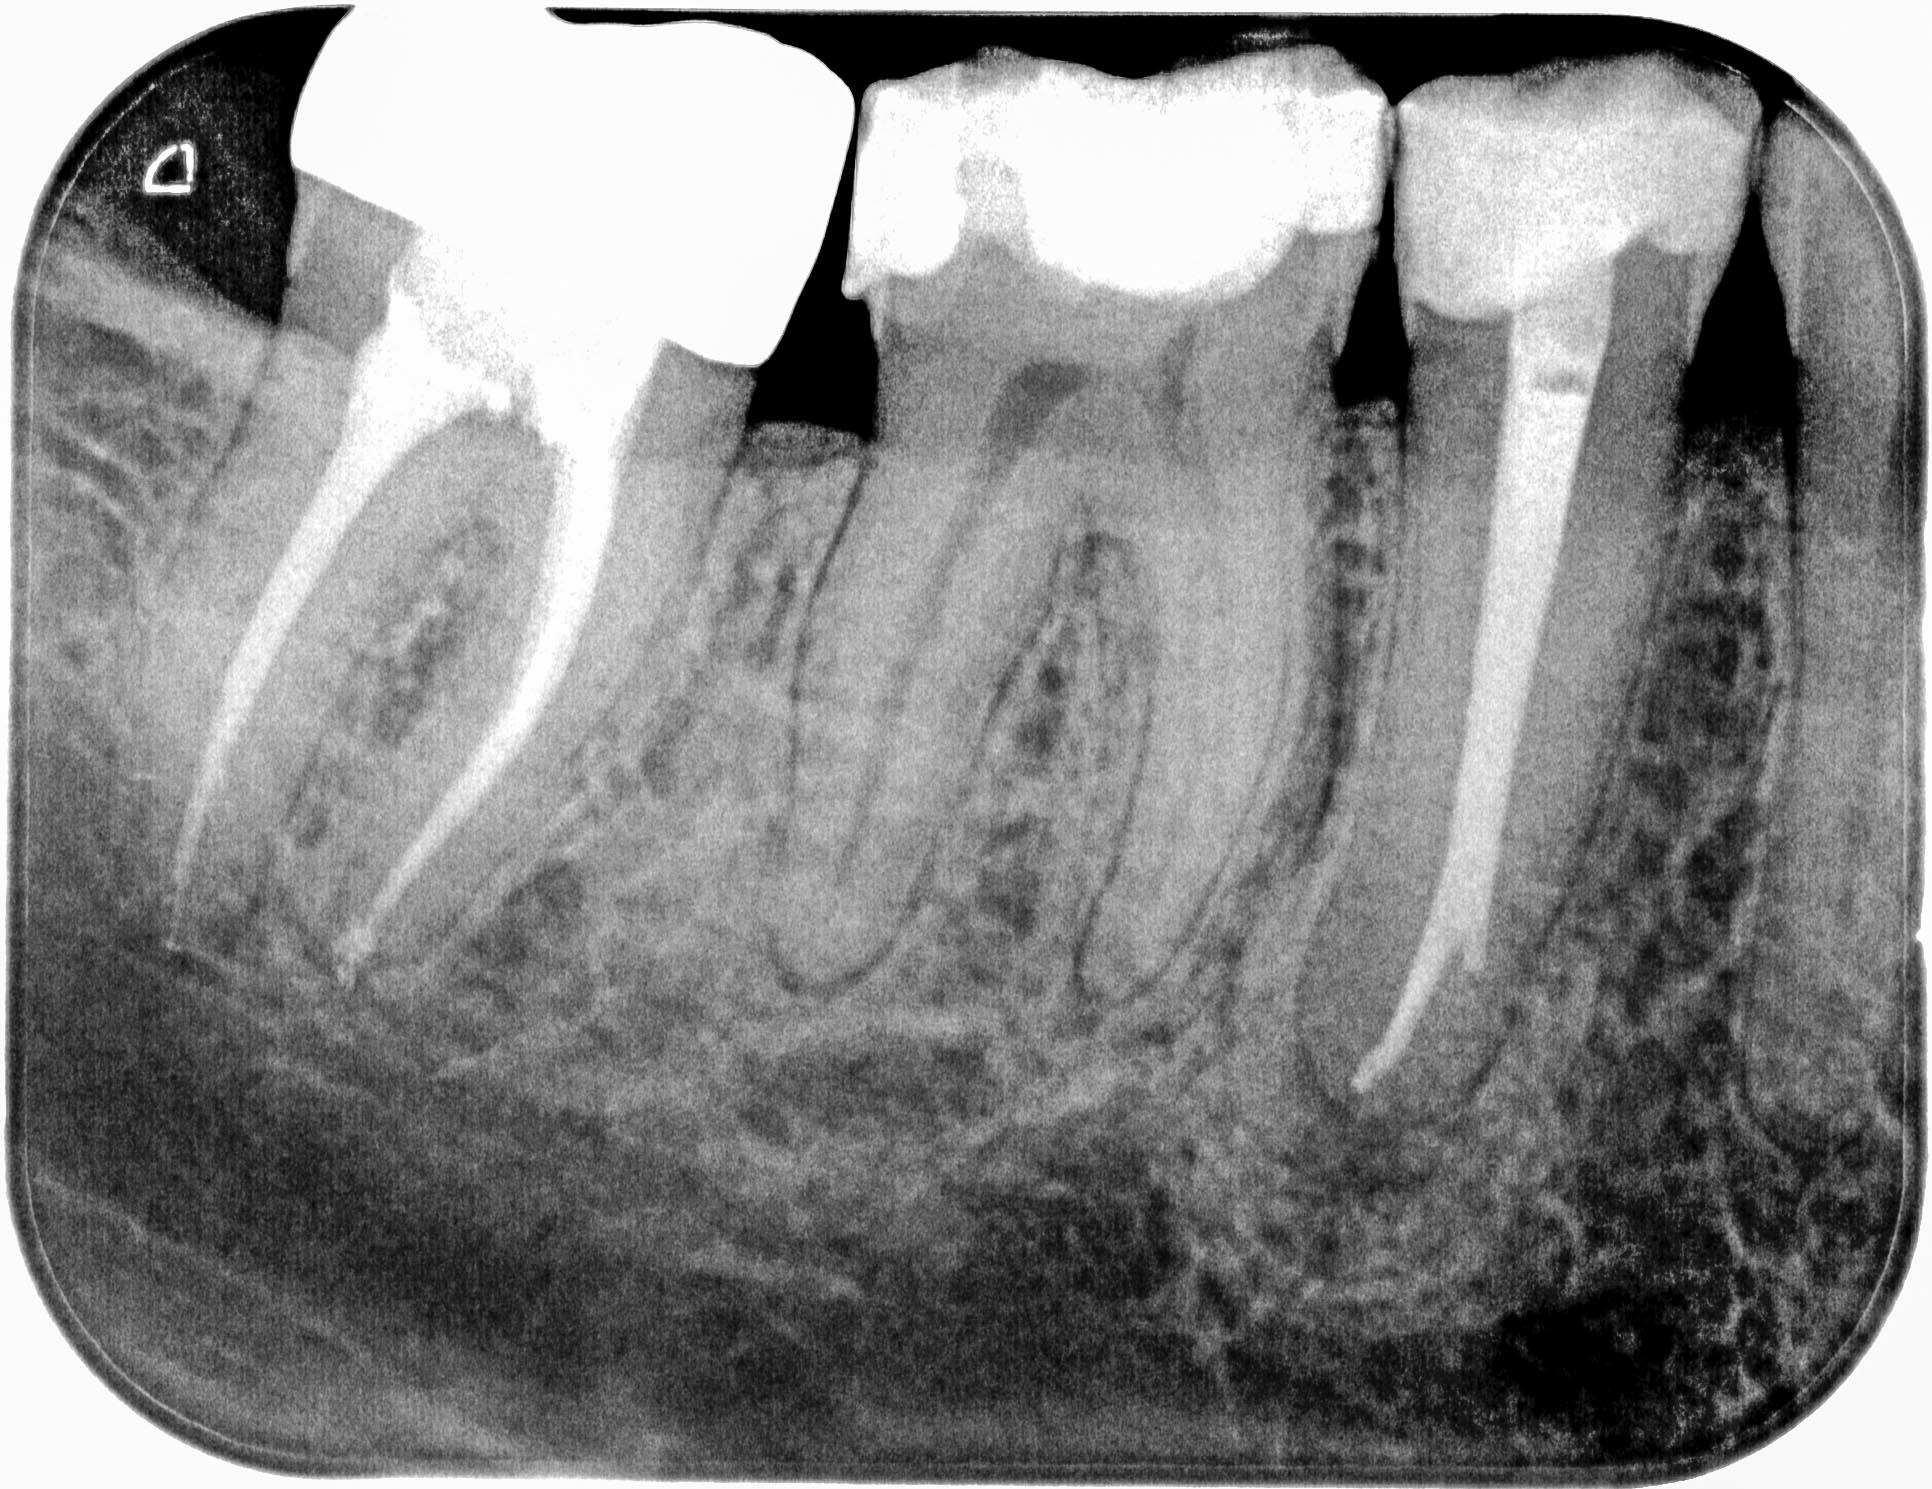

3 Haselnüsse (2)